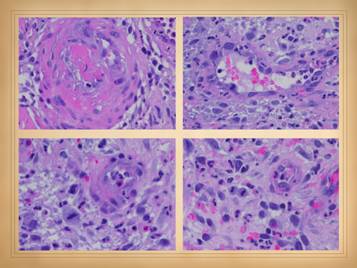

30

This slide shows the features of acute and early ulcers.  Since this is the phase of active ulceration, you are witnessing the destruction as it happens, as the disease causes thrombosis-infarction or immunity-inflammation-lysis.  You are catching the culprit in the act, so you are likely to see signs specific to the particular disease, along with the generic signs of active inflammation and thrombosis, and of active infarction, tissue lysis, and ulceration.

Local findings:  These are the features of the necrosis and active ulceration, in the wounds themselves and in their immediate surroundings.  They may be focal or multifocal, but when multiple or multifocal, this is usually a dependable sign of autoimmune ulceration.  There may be inflammatory lysis and dissolution of tissue versus microthrombotic infarction, which can give insights as to which diagnosis or mechanism of disease predominates.  Whether the periwound is inflamed versus bland also tends to discriminate thrombo-occlusive lesions from immune-inflammatory ones.  Signs of vasculitis, synovitis, panniculitis, dermatitis, cicatritis, and even arthritis and serositis can reveal the autoimmune nature of the problem and imply which specific disease or syndrome is active.  General and systemic findings:  generalized inflammation, edema, dermatitis, panniculitis, vascular stasis, systemic and disease-specific symptoms, pain, malaise.  Remember, during these acute phases of ulceration the primary disease is active, so patients will often have a multitude of symptoms.

In the cases shown of early and developing wounds, note the changes in the ulcers and surrounding tissues.  They predominantly show an inflammatory-lytic pattern of ulceration as opposed to thrombo-infarctive necrosis.  Top left:  crst-mctd, dissolution of wound margins, vascular stasis and cyanosis, acute dermatitis.  Top right:  rheumatoid, multifocal ulceration, periwound inflammation, dissolution of skin without dry eschar, panniculopathy.  Bottom left:  rheumatoid, progressive dissolution of skin and fascias, no eschar, involvement of old scar, ulceration along tendon sheath and exposure of peroneus tendon.  Bottom center:  rheumatoid, multifocal ulceration, multifocal stasis and cyanosis in advance of infarcts and ulcers, generalized panniculitis and edema, active necrosis and erosion at skin margins, no eschar.  Bottom right:  Sjögren’s, loss of adipose panniculus, active necrosis and ulceration at margins, exposure of peroneus muscle (synovitis).  This last example has black necrosis and little inflammation in the periwound (no erythema nor edema), making this mainly a thrombo-infarctive pattern of ulceration, implying some type of micro-occlusive pathology.  The patient has classic Sjögren’s, but she also had a very high fibrinogen and low protein C, a good hypercoagulable explanation for the thrombo-infarctive pattern of the wound.  This is the same patient in the same position (lower right) on the previous slide.  That was her opposite leg, with acute diffuse erythema-nodosum-like panniculitis, along with generalized signs and symptoms of active inflammation, immunity, and disease flare up.  As will be shown later, this duality of pathologies – inflammatory and thrombotic – is common, and many patients will have mixed findings and features in their wounds, both inflammation-lysis and thrombosis-infarction.